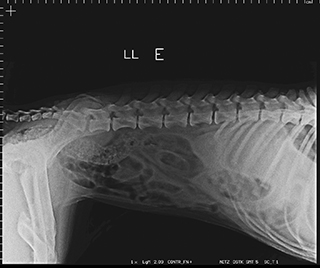

Radiologia Digital Direta / Digital Radiography

As radiografias geradas digitalmente podem ser transmitidas para iPad Apple®, notebooks e smartphones.

iPad com tela Retina Apple® possibilita a visualização das imagens com maior qualidade diagnóstica.

Envio Digital Automático (EDA) permite a distribuição das radiografias sem necessidade de impressão.

O responsável pelo paciente pode receber as radiografias em seu smartphone ou computador.

Radiologistas podem receber as imagens por e-mail para laudo, de forma prática. 100% DIGITAL